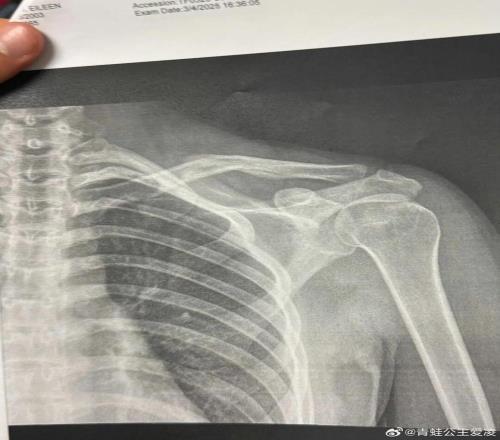

2025年是谷爱凌口中“职业生涯最艰难的一年”,三月她在阿斯本训练中遭遇严重的脑震荡,导致急性颅内出血、癫痫发作,一度失去意识五分钟,如此严重的伤病让她一度认为自己再也醒不过来。八月的意外受伤让她错过了亚冬会,十一月复出后的失利又引发外界的质疑,种种猜测都让她的心理得到深刻的锤炼。